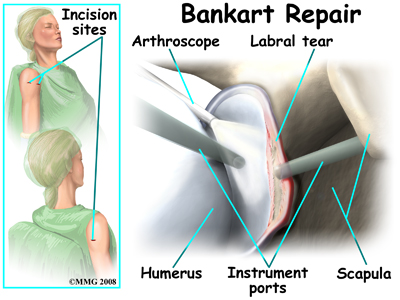

Bankart Repair

The most common method for surgically stabilizing a shoulder that is prone to anterior dislocations is the Bankart repair. In the past, the Bankart repair was done through a large incision made in the front (anterior) shoulder joint. This required damage to a great deal of normal tissue in order for the surgeon to be able to see the damaged portion of the joint capsule. The procedure was difficult and usually involved an attempt to sew or staple the ligaments on the front side of the joint back into their original position.

The arthroscope has changed all that.

An arthroscope is a special type instrument designed to look into a joint, or other space, inside the body. The arthroscope itself is a slender metal tube smaller than a pencil. Inside the metal tube are special strands of glass called fiberoptics. These small strands of glass form a lens that allows one to look into the tube on one end and see what is on the other side - inside the space. This is similar to a microscope or telescope. In the early days of arthroscopy, the surgeon actually looked into one end of the tube. Today, the arthroscope is attached to a small TV camera. The surgeon can watch the TV screen while the arthroscope is moved around in the joint. Using the ability to see inside the joint, the surgeon can then place other instruments into the joint and perform surgery while watching what is happening on the TV screen.

The arthroscope lets the surgeon work in the joint through a very small incision. This may result in less damage to the normal tissues surrounding the joint, leading to faster healing and recovery. If your surgery is done with the arthroscope, you may be able to go home the same day.

To perform the Bankart type repair using the arthroscope, several small incisions are made to insert the arthroscope and special instruments needed to complete the procedure. These incisions are small, usually about one-quarter inch long. It may be necessary to make three or four incisions around the shoulder to allow the arthroscope to be moved to different locations to see different areas of the shoulder.

A small plastic, or metal, tube is inserted into the shoulder and connected with sterile plastic tubing to a special pump. Another small tube allows the fluid to be removed from the joint. This pump continuously fills the shoulder joint with sterile saline (salt water) fluid. This constant flow of fluid through the joint inflates the joint and washes any blood and debris from the joint as the surgery is performed.